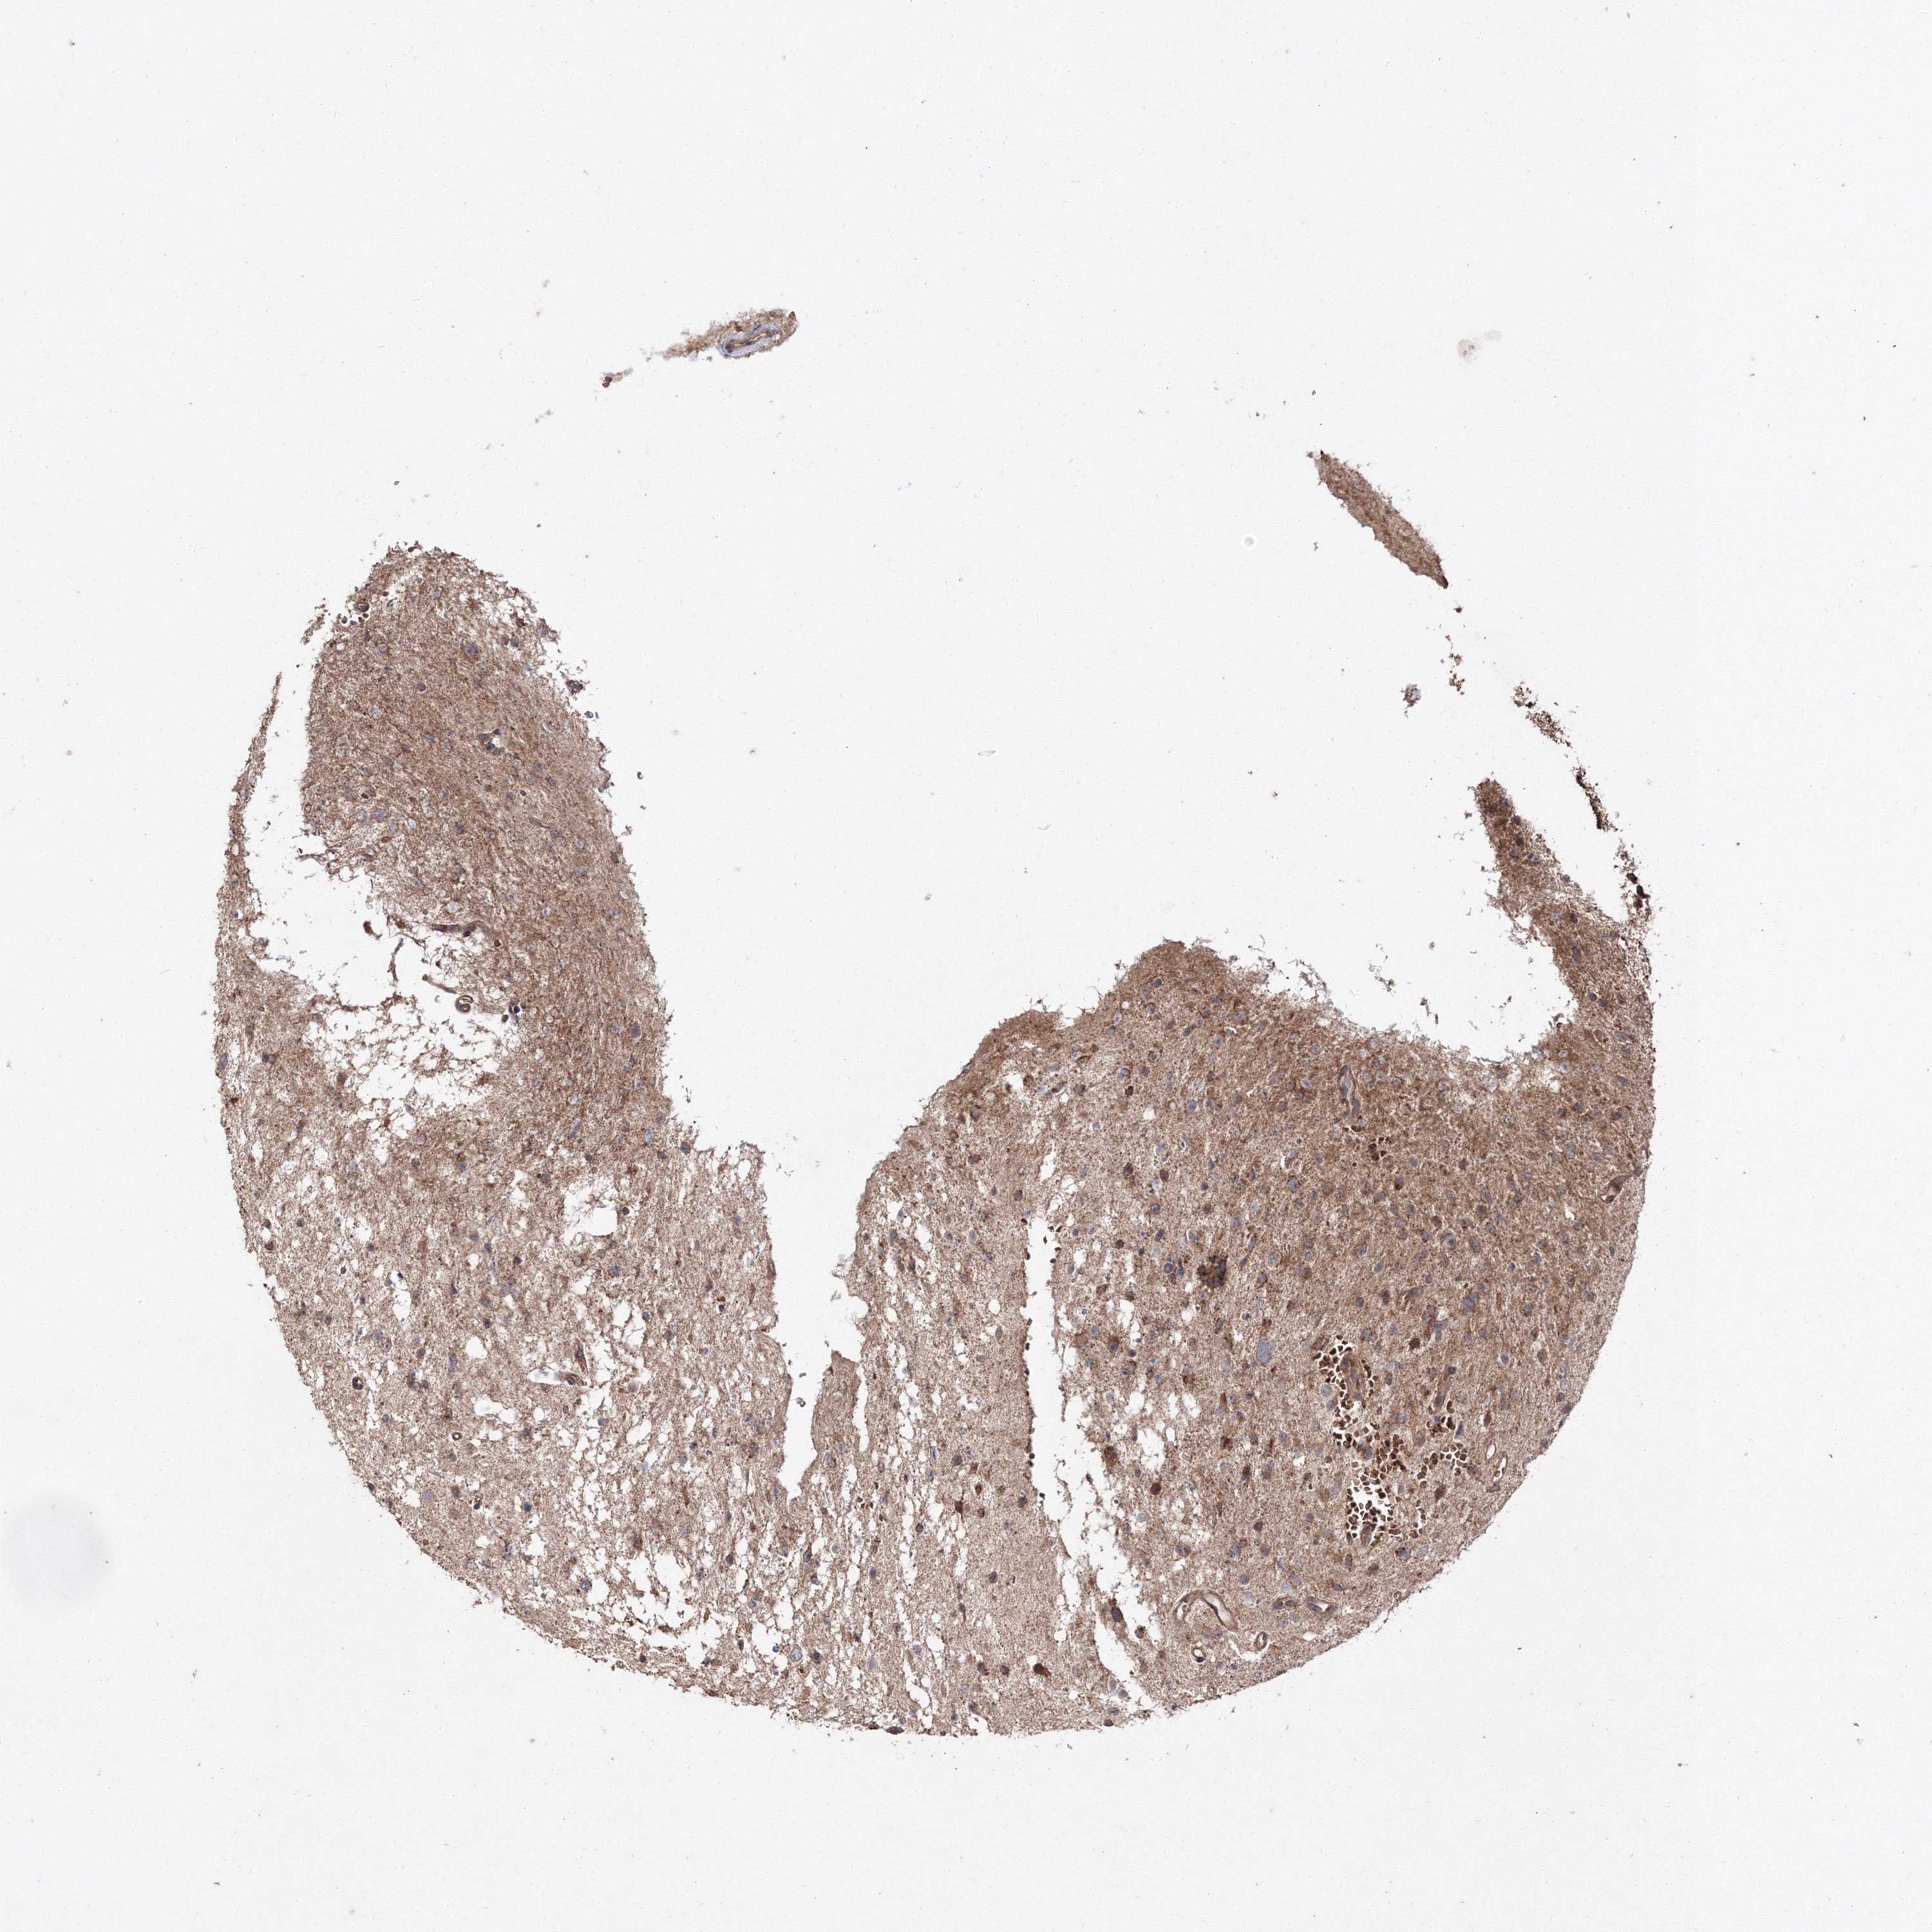

GLIOMA - Protein expressioni

A mouse-over function shows sample information and annotation data. Click on an image to view it in a full screen mode. Samples can be filtered based on level of antibody staining by selecting one or several of the following categories: high, medium, low and not detected. The assay and annotation is described here.

Note that samples used for immunohistochemistry by the Human Protein Atlas do not correspond to samples in the TCGA dataset.

Antibody stainingi

Antibody staining in the annotated cell types in the current human tissue is reported as not detected, low, medium, or high, based on conventional immunohistochemistry profiling in selected tissues. This score is based on the combination of the staining intensity and fraction of stained cells.

Each image is clickable and will lead to virtual microscopy that enables deeper exploration of all samples and also displays staining intensity scores, fraction scores and subcellular localization as well as patient and tissue information for each sample.

Antibody HPA037525

Antibody HPA037526

Staining

High

Medium

Low

Not detected

Intensity

Strong

Moderate

Weak

Negative

Quantity

>75%

75%-25%

<25%

None

Location

Nuclear

Cytoplasmic/membranous

Cytoplasmic/membranous,nuclear

Glioma, malignant, Low grade

Glioma, malignant, High grade

Glioblastoma, NOS